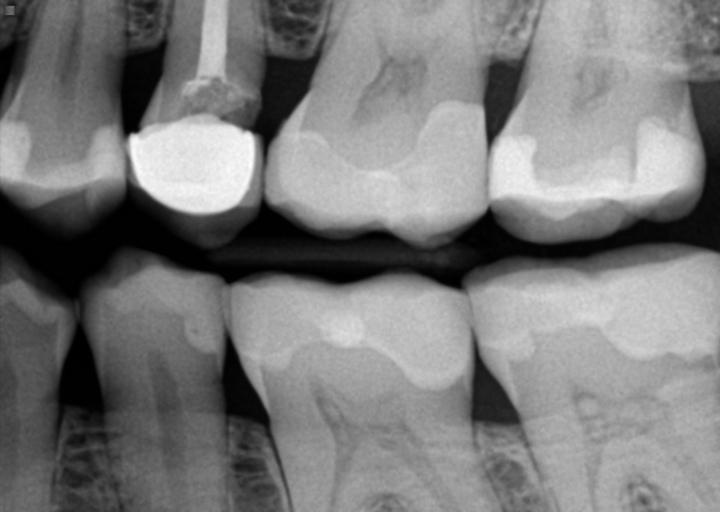

I have a crack in the lower back of my temp crown and light blood is coming from their

I have a crack in the lower back of my temp crown and light blood is coming from their It has happened twice now, yesterday and today There is also a slight pain when drinking water and both time the bleeding was just after I drank water I can’t see my dentist until next week I have this temp crown for 3 years now and have to wait another year to get a permanent one due to financial problems and nerve has also been removed in this particular tooth due to abscess in the past HELP PLEASE!!!!! Is it serious? What’s happening? Why is their blood?